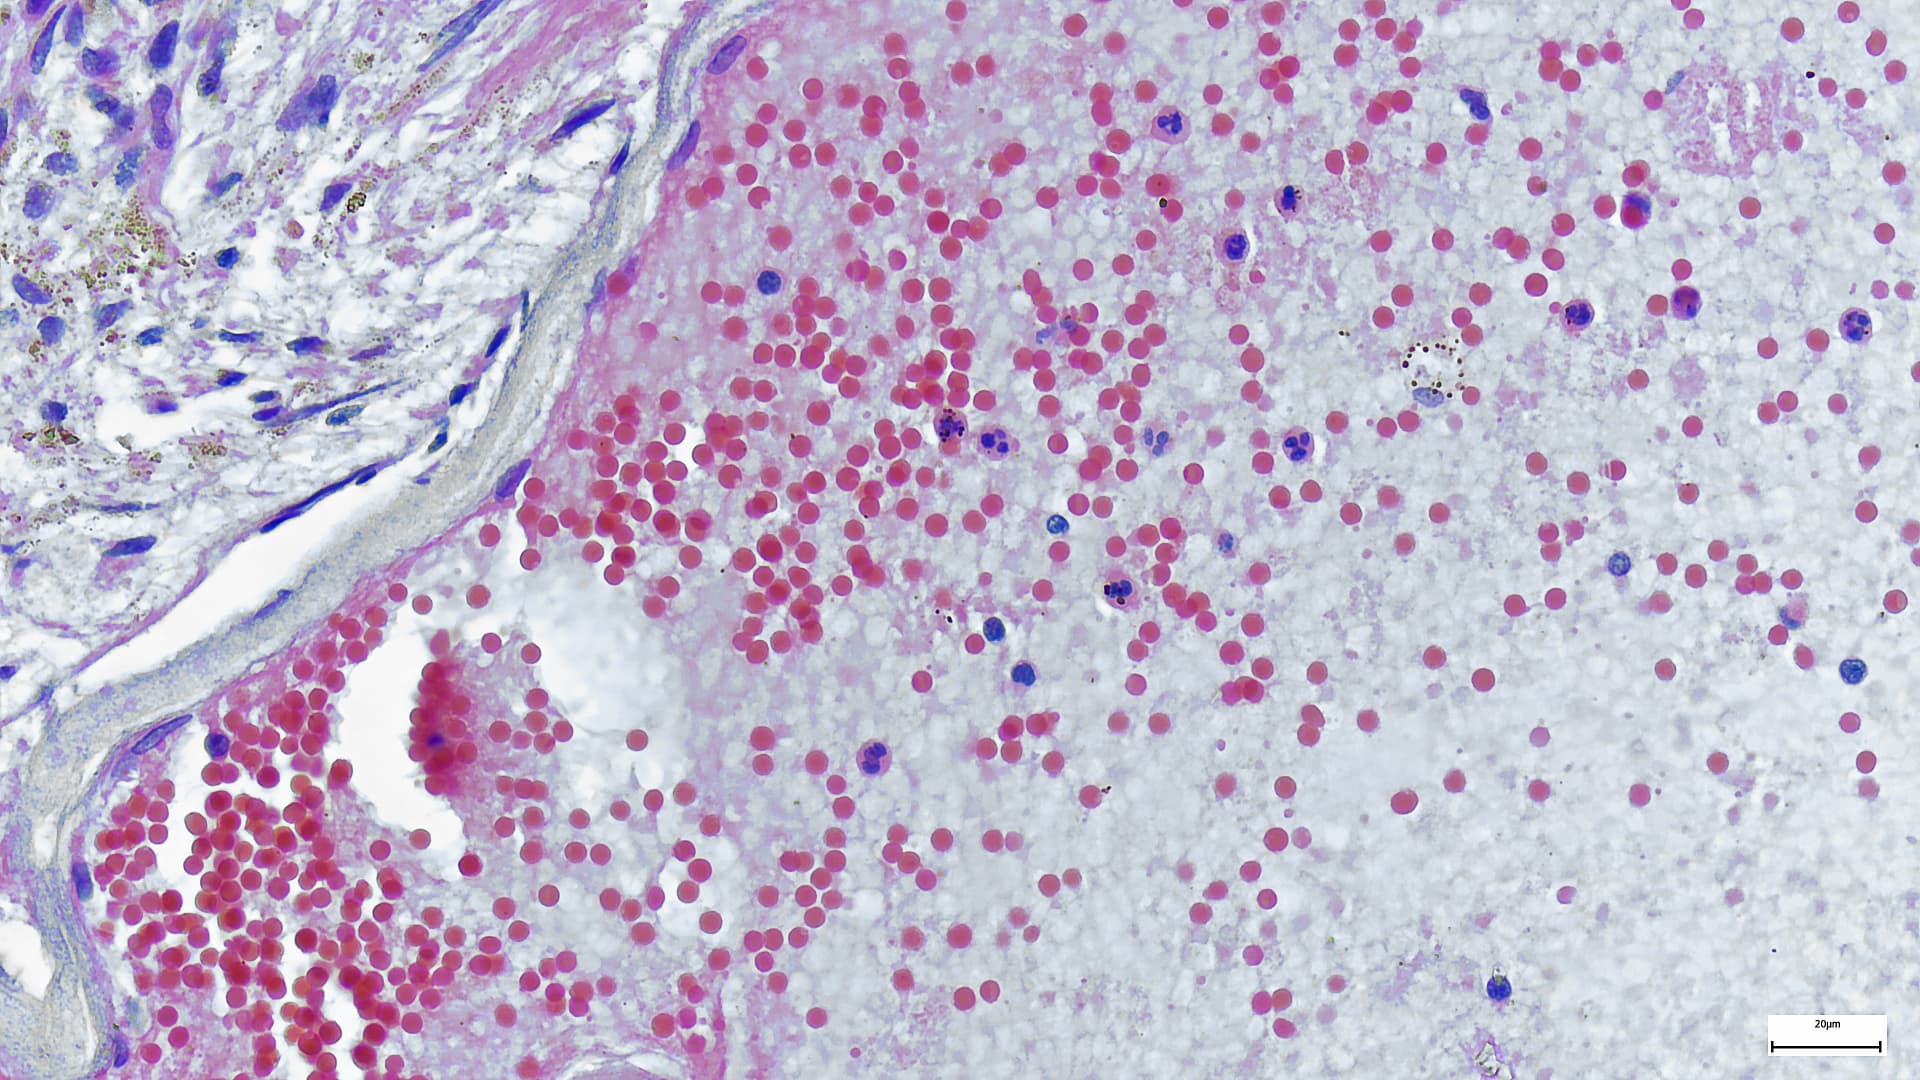

Mpox is a viral infection which spreads through close contact, including sexual contact. It causes flu-like symptoms, including fever, chills and muscle aches, as well as pus-filled lesions. Although it is usually mild, it can be fatal.